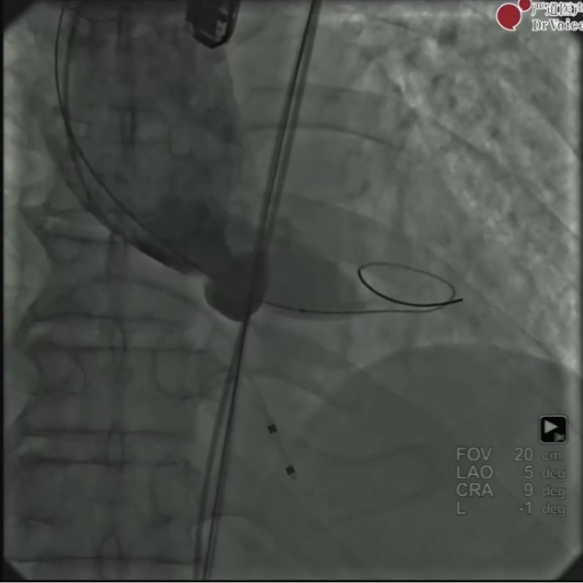

主动脉CTA提示:Type 1型二叶瓣,重度钙化且钙化分布不均匀,左右瓣叶粘连,主动脉根部周径86.8mm,直径27.6mm,LCA高度10.9mm,RCA高度14.8mm,STJ矮小,存在冠脉阻塞风险。同时该患者为横位心,升主动脉增宽,有破裂风险。

术前主动脉根部造影